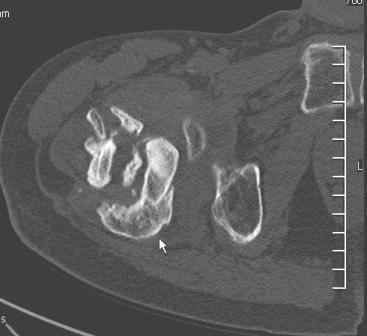

Больной Н. 44 года травма 1,5 года назад июнь 2008 года чрез-под вертельный перелом правого бедра. Во время лечения у больного развился алк. делирий, проводилось консервативное лечение перелома.

Беспокоят боли, укорочение конечности.Укорочение 3 см. Ногу поднимает, сгибание ограничено, ротационные движения в полном объеме.На КТ перелом сросся за счет костной мозоли.Что делать?

Протез? Если «да» Можно ли обойтись стандартной ножкой Corail?

Или межвертельная остеотомия?

мне кажется перелом не сросся, думаю,вальгизирующая остеотомия. возможно с последующим удлинением решит проблему. Эндопротезировать в такой ситуации не нужно.

Уважаемый Глеб, боли из-за ложного сустава шейки бедра. Сращения там нет.

Тазобедренный сустав сохранный и возраст пациента позволяет побороться. Согласен с Максимом, попробуйте остеотостеотомию.

Уважаемый Глеб! Укорочение наверное побольше, да и наружно-ротационная установка скорее всего присутствует. Суставная щель прекрасная, головка живее всех живых. Ратую за подвертельную с латерализацией: исключает нарушение механической оси («исключает вальгус в коленe»), максимально удлиняет без натяжения m.iliacus. Для иллюстрации остеотомия-переделка (слава богу не автопеределка) у мужчины 65 лет.